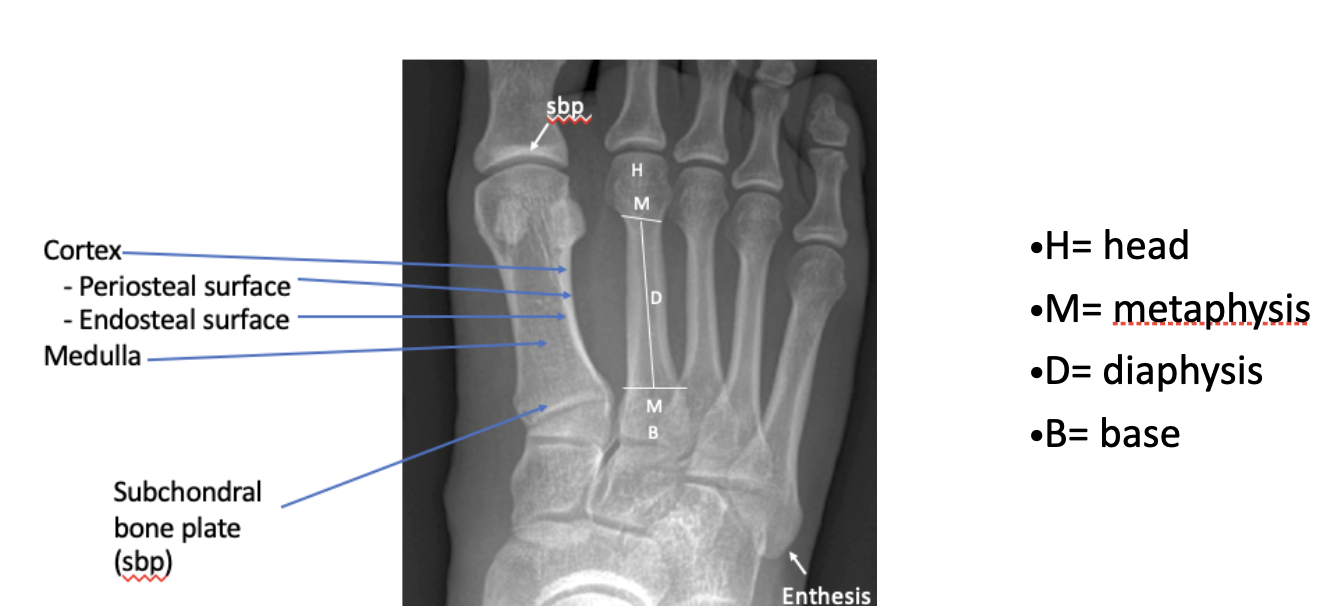

What are bone's four primary radiographic attributes?

position, form, density, architecture